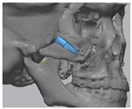

2.2. Computer-Aided Virtual Surgery, Design, and Fabrication of Patient-Specific Devices

2.3. Surgical Procedure